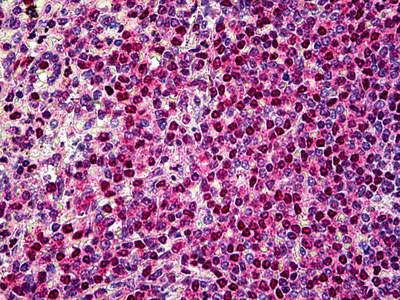

Anti-PIM1 antibody IHC of human spleen. |